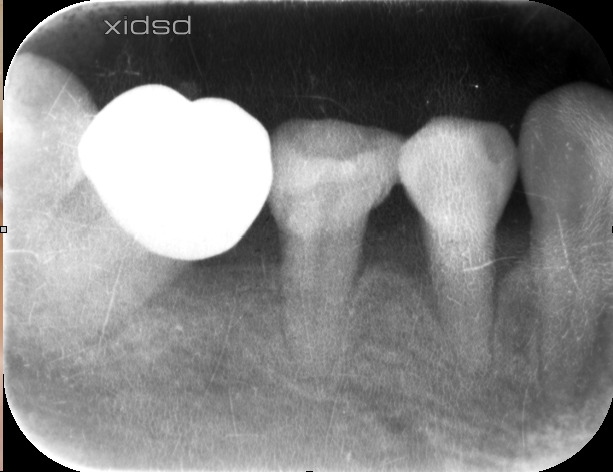

術後約1年

見て下さい!骨が再生しています。歯周ポケットも3mmまで回復。

勿論この治療、歯茎を切っていません。再生材料も使っておりません。

根の表面の顕微鏡によるクリーニングと血餅を安定させただけです。